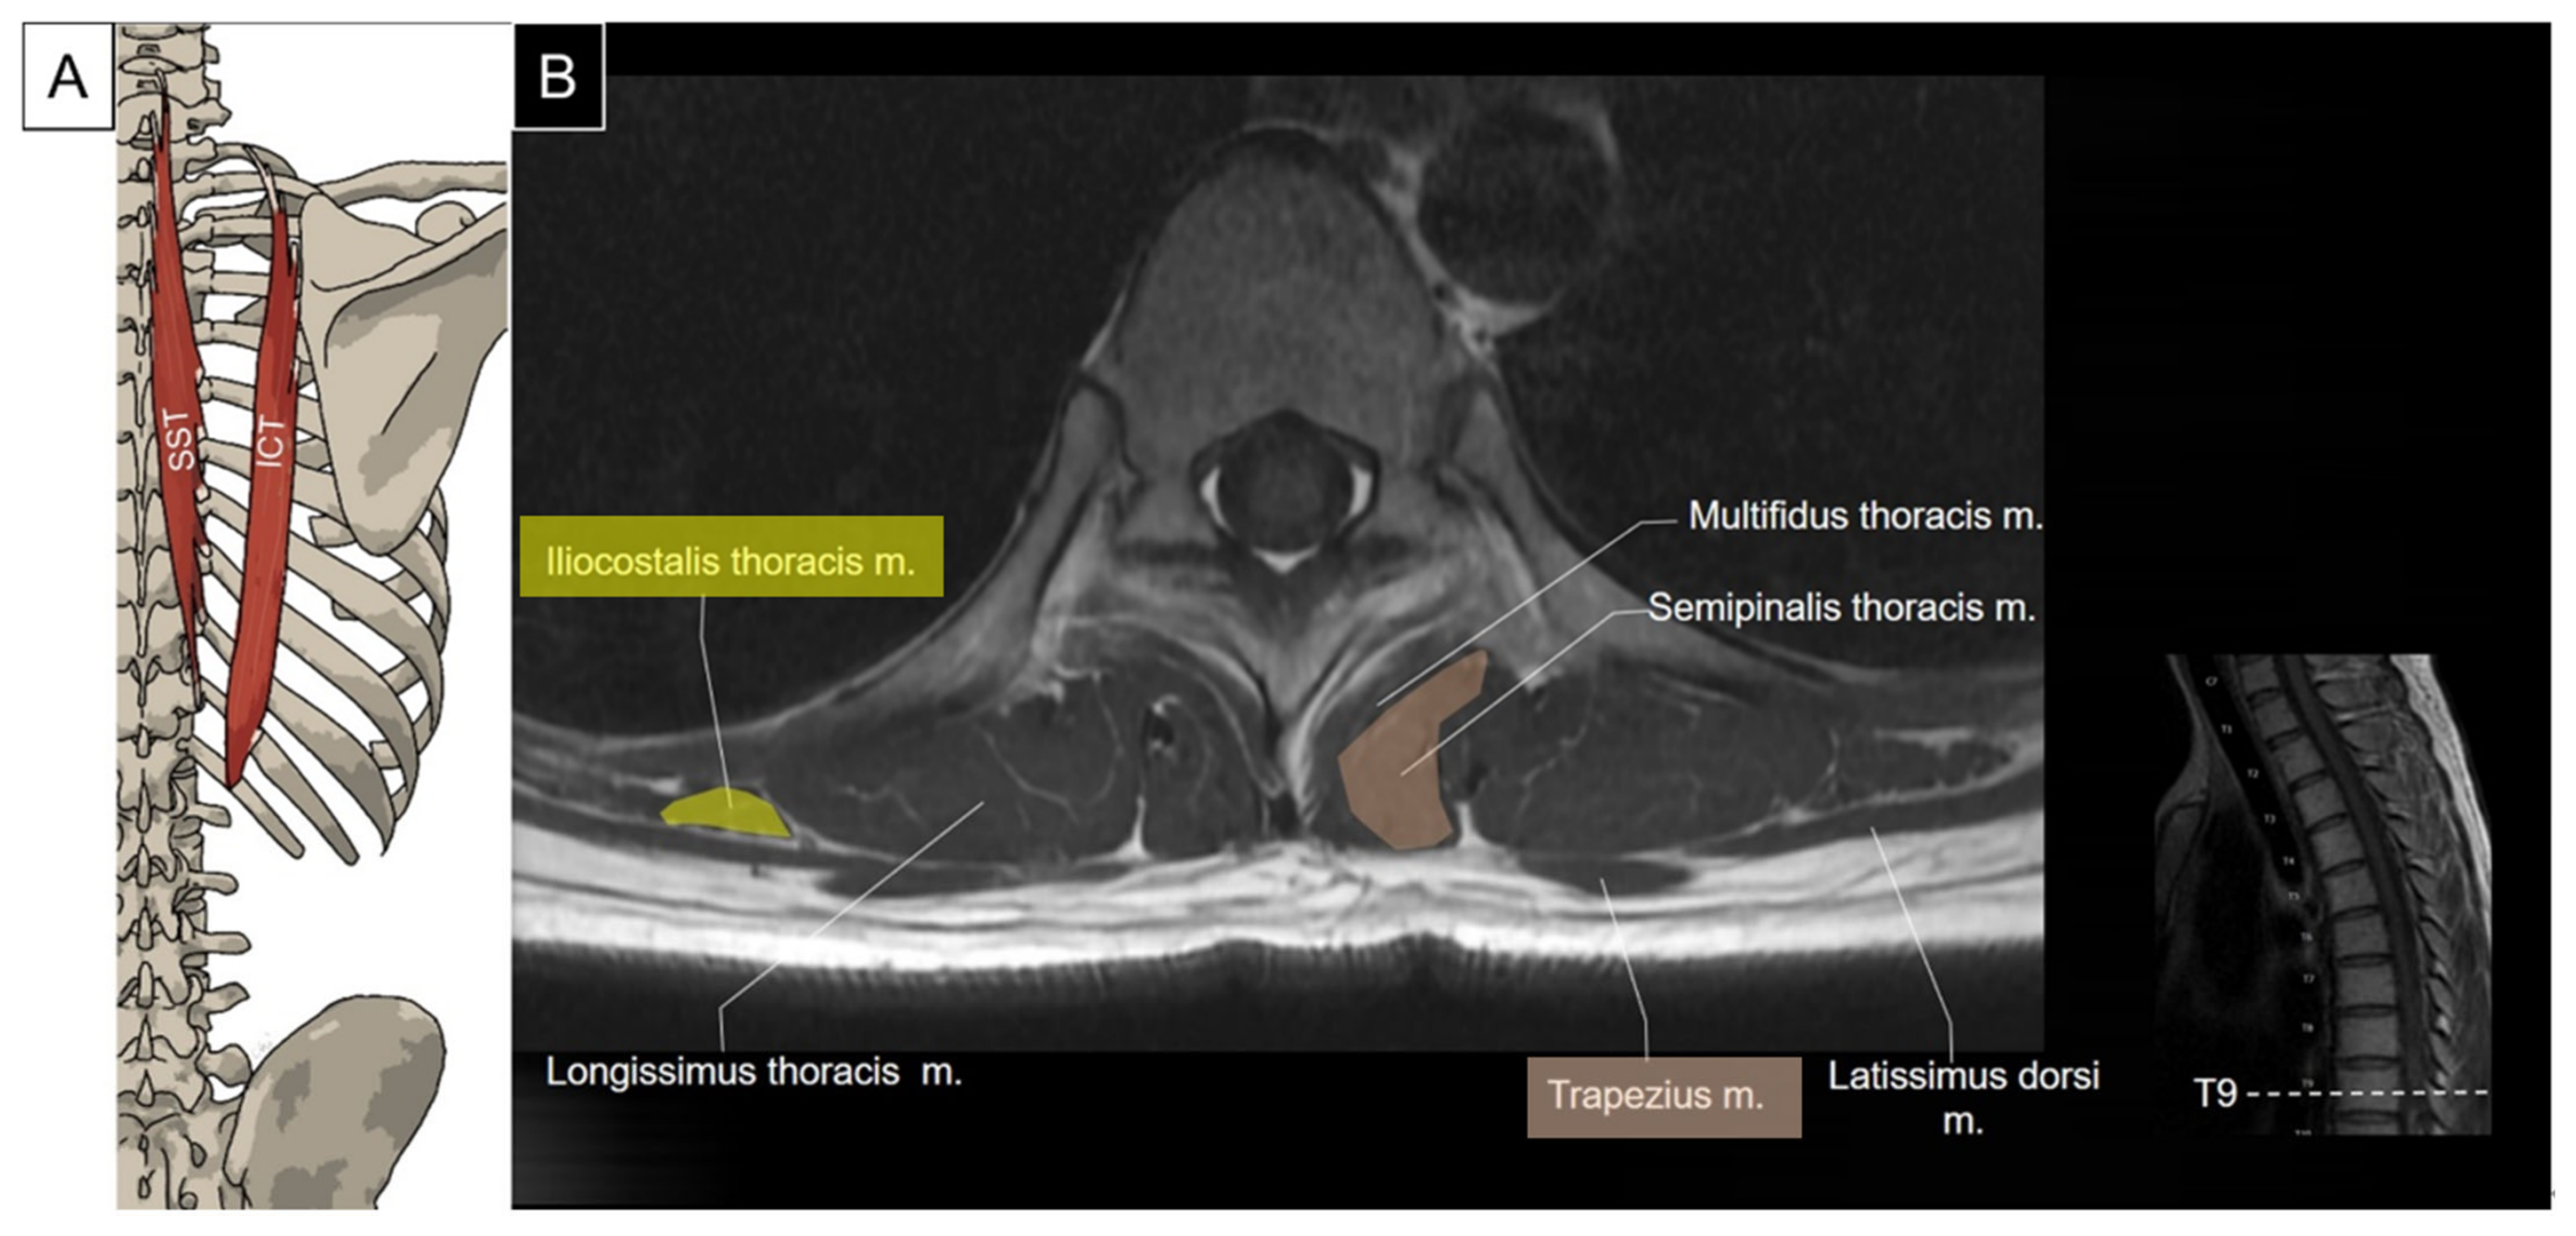

5.1.1. Anatomy

5.1.2. Sonographic Scanning

5.1.3. Clinical Relevance